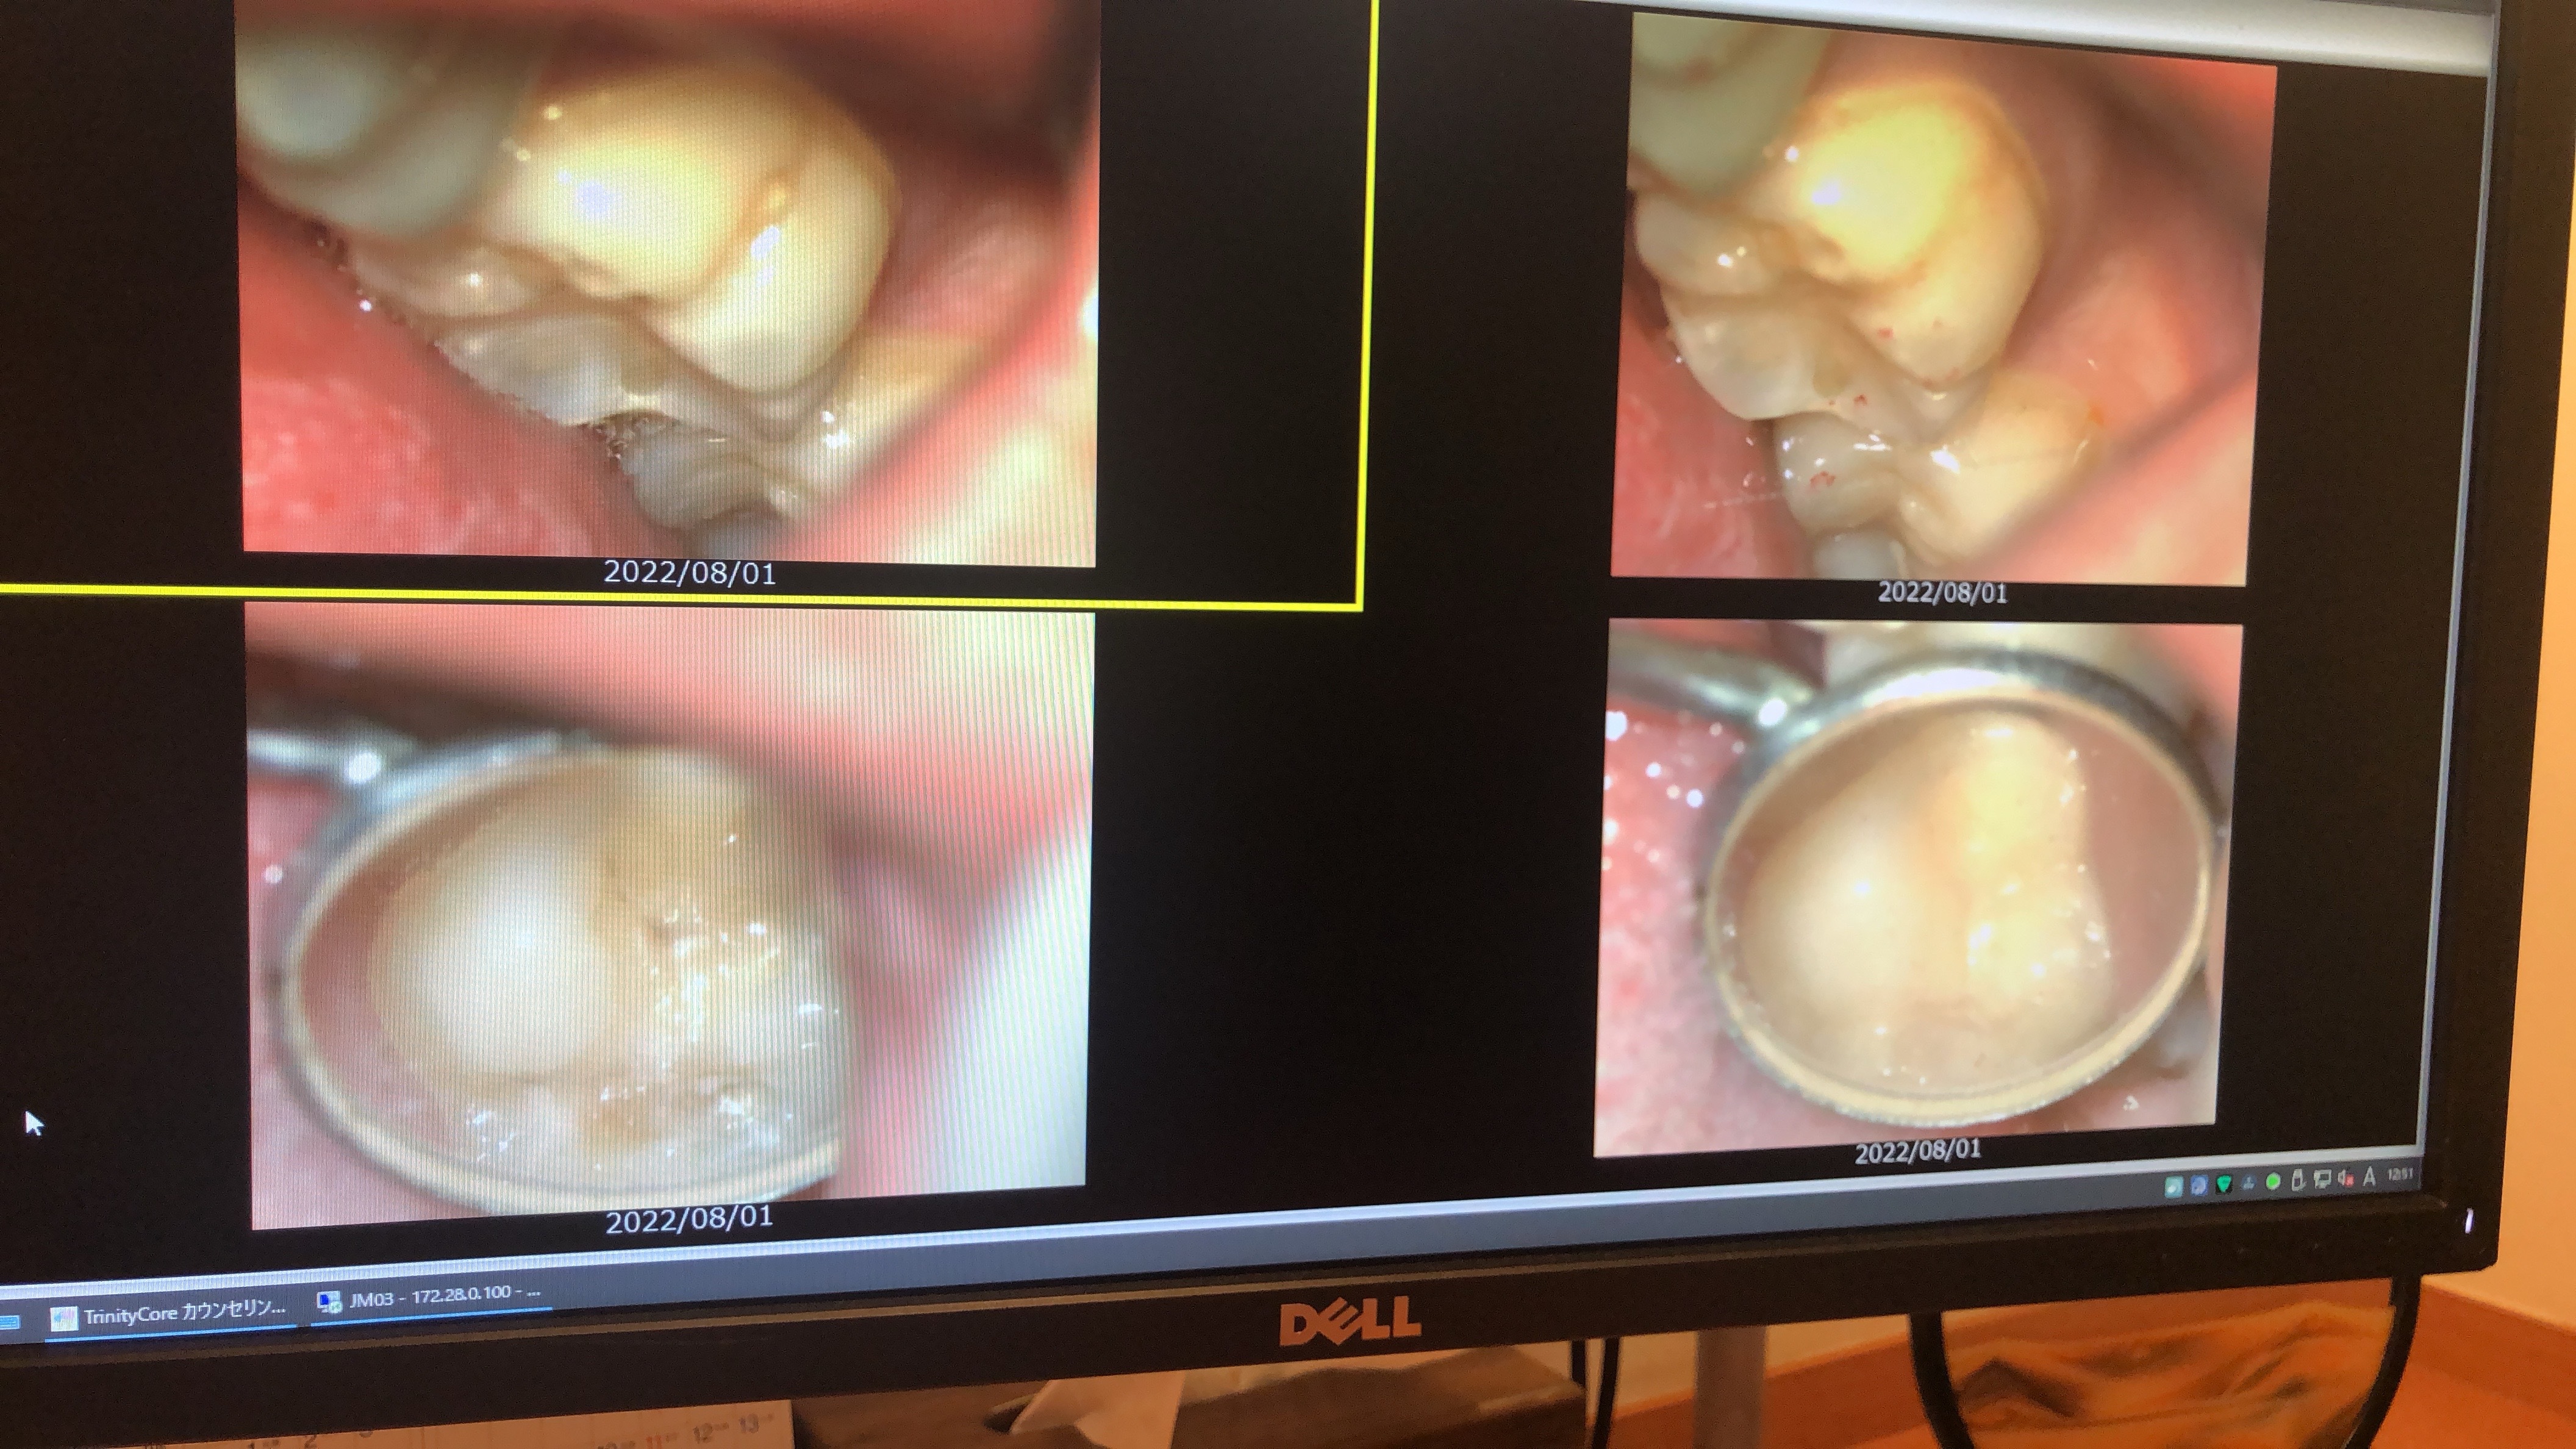

被せ物が気になる方は必見!?

セラミックの被せ物を装着した患者様になります。 技工士さんに色や形も相談して作製してもらう...